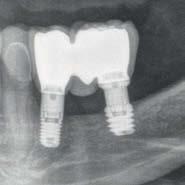

Fueron reclutados de forma retrospectiva pacientes en los que se hubiesen realizado ambas

técnicas de abordaje de seno maxilar: elevación convencional o la inserción de implantes cortos y extra-cortos mediante elevación transcrestal, desde enero de 2010 en adelante. Todos los pacientes fueron estudiados antes de la inserción de los implantes mediante modelos diagnósticos, exploración intraoral y realización de un TAC dental (Conebeam) analizado posteriormente mediante un software específico (BTI-Scan II).

Los implantes y la elevación de seno por abordaje lateral fueron colocados por un mismo cirujano. La ventana de acceso lateral se realizó, en todos los casos, con el